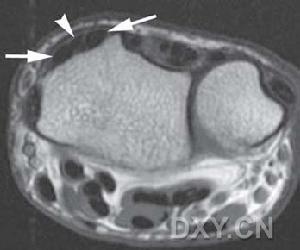

3. 肌肉切片檢查:有一些特異及非特異性的變化,除了肌肉進行性萎縮變化,另外可見第一型肌纖維細胞萎縮及及細胞核內移動現象。